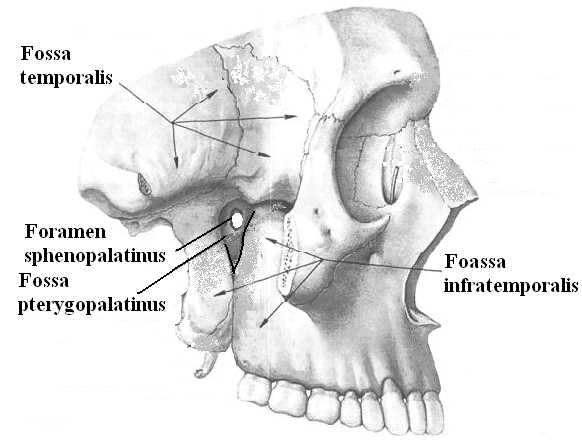

Анатомические особенности: фотографии ямок черепа, височной и подвисочной крылонебной

:background_color(FFFFFF):format(jpeg)/images/article/ganglion-pterygopalatinum/Olb5PmzrqNm15b1YA8H5w_Pterygopalatine_ganglion_m.png)